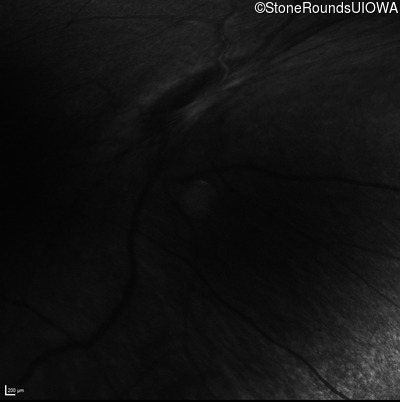

Infrared Fundus Photograph - Right - No Light Perception

Exemplar